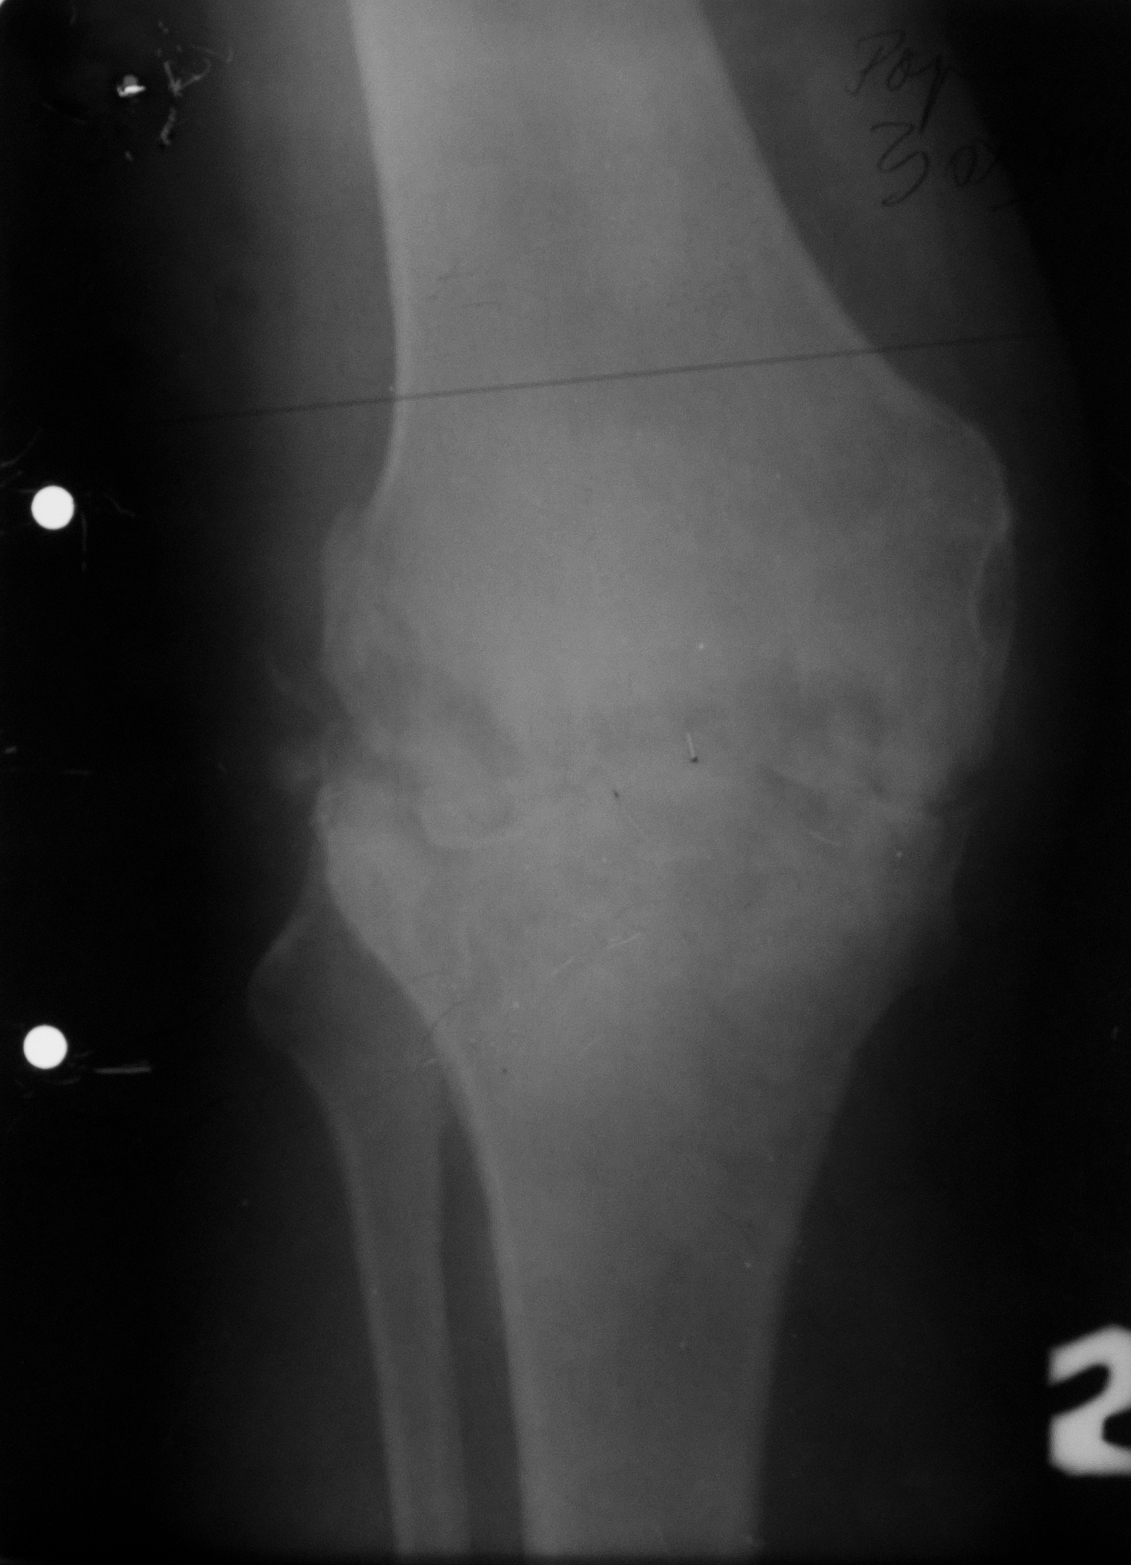

TUBERCULOZA GENUNCHIULUI

Radiografie de genunchi (Rx.de fata)

Nu se vede niciun spatiu articular, lipseste total

Suprafetele articulare sunt neregulate si sunt punti osoase ce trec dintr-o parte in cealalta,deci e o anchiloza radiologica, datorata osteoartritei (cu distrugerea atat a tesutului cartilaginos, cat si a osului spongios de dedesubt)

TUBERCULOZA GENUNCHIULUI

RX de profil